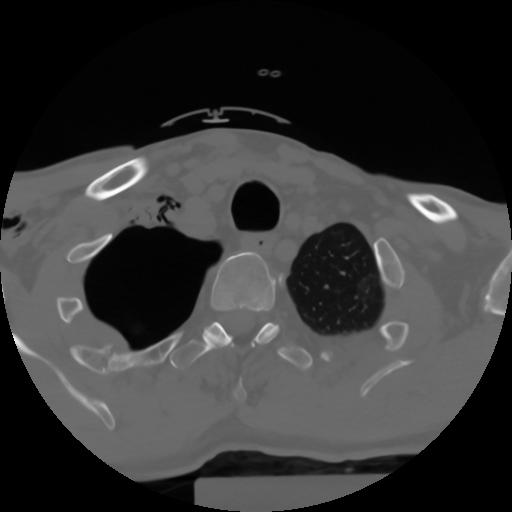

10 P.BLANDAS,,Axial,2.0,P.BLANDAS,,